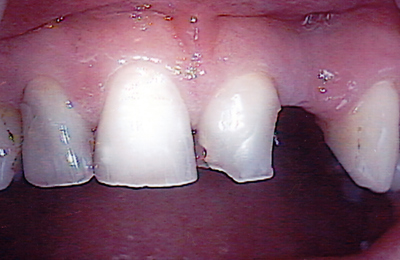

See the results

Drag the sliders below to see some of the amazing results achieved by other Lumino patients and our experienced team of dentists.

Bridge 2 Before Bridge 2 After